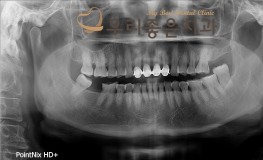

우리좋은치과 치아 상실 및 골소실 → 뼈이식 및 임플란트 보철 치료(김**2017...

No.295

임플란트

2019-05-31

1538